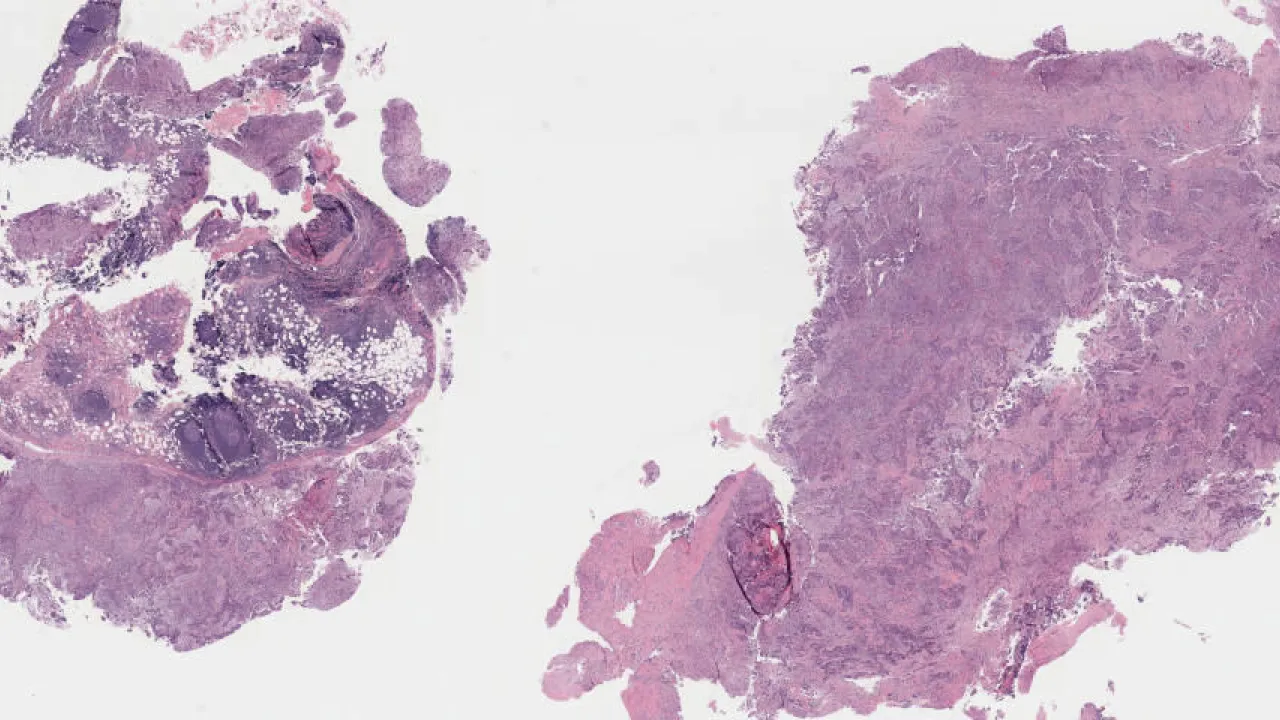

Lymph Nodes, Mantle cell lymphoma, H&E stain